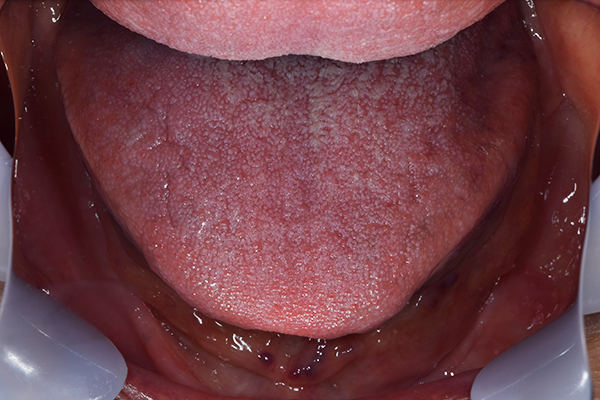

残っている歯があれば、どういう状態で、それは残せるのか?、また歯がない場合は歯ぐきの状態はどうなのか?やせているのか?骨はたくさんあるのか?入れ歯は安定しそうか?歯ぐきでぶよぶよしたところはないか?舌は大きいか?今お使いの入れ歯が当たって傷になっていないか?骨の隆起はないか?嘔吐反射はないか?唇のラインは?などをみていきます。

お口に入っている状態です。嘔吐反射が強かったため、うわあごの部分をくり抜いて作っています。

嘔吐反射が強く、普通の上顎の入れ歯を入れた時の違和感が強いため、口蓋部をくり抜いてつくっていきました。